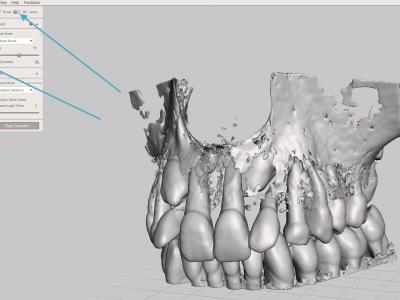

- Etape de nettoyage : il s'agit d'enlever tous les fragments osseux ou les zones non désirées. C'est l'étape la plus longue ! (Il faut penser à sauvegarder régulièrement pour éviter des accidents).

Différents séquences d'outils vont être utiles :

Sélectionner la surface de zone à éliminer avec l'outil "Select" "Brush", puis les supprimer avec le raccourci clavier "X"

Sélectionner une zone complète à éliminer avec l'outil "Select" "Lasso", puis les supprimer avec le raccourci clavier "X"

Pour éliminer les fragments non reliés : sélectionner une ou plusieurs petites zones à garder (dents par exemple) avec l'outil "Select" "Brush", puis opération "Expand to connected", puis inversion de la sélection avec la touche "I", puis les supprimer avec le raccourci clavier "X"

- Etape de réparation : réparer les "trous" du maillage 3D avec l'outil "Inspector" et "Auto repair all" afin de ne pas avoir d'erreurs d'impression

- Etape de finitions : reboucher des manques, adoucir des pics ou des crêtes avec les différents outils "Sculpt"

- Etape de solidarisation : si certaines dents ne sont pas en contact avec d'autres, les solidariser avec l'adjonction de cylindres, puis fusionner les éléments avec l'outil "combine"

- Exporter le fichier STL à imprimer